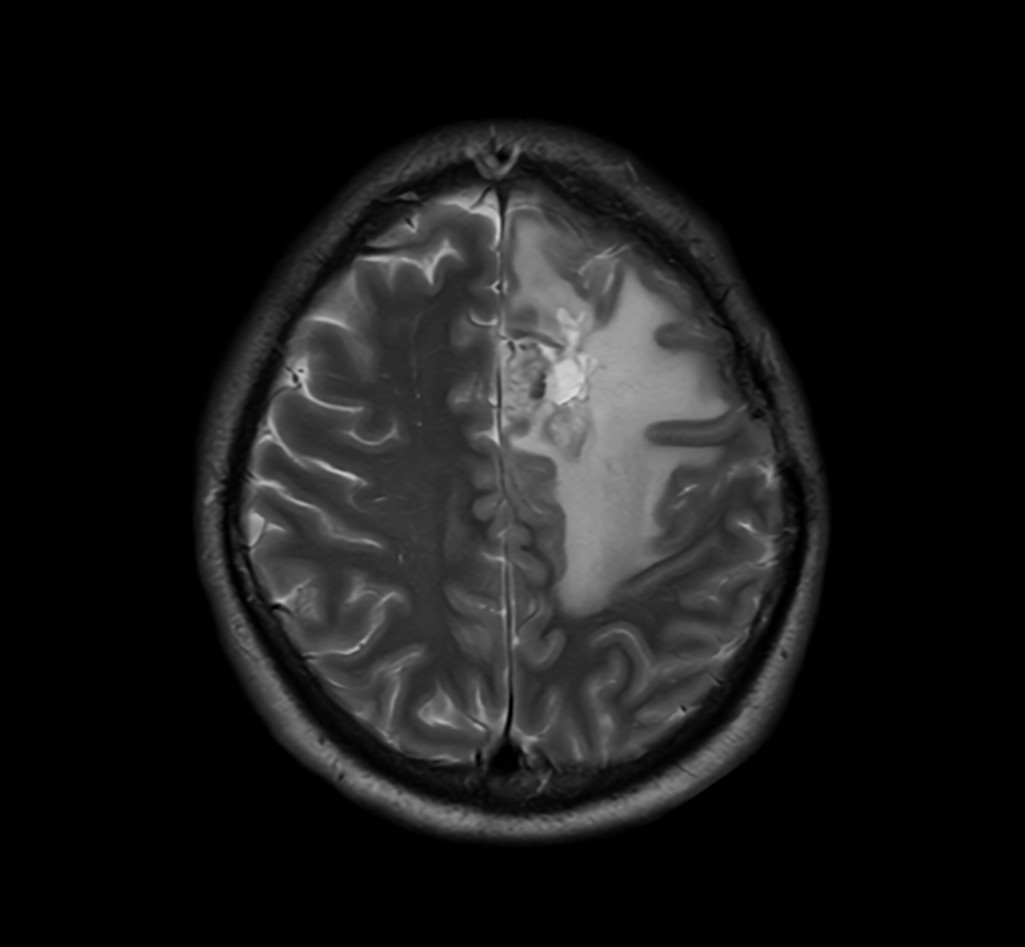

SmartSpeed Precise imaging for brain with glioblastoma

Kyushu University Hospital Japan